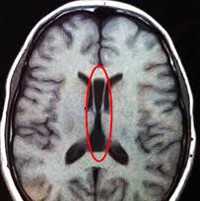

Важной находкой при АМТ на МРТ является параллельная ориентация тел боковых желудочков по отношению друг к другу (рис. 4, а), расширенные фронтальные отделы желудочков, так называемый «симптом ухвата».

Рис. 4. МРТ головного мозга больной К., 4 года. АМТ. Аксиальная проекция: а — аномальная параллельная ориентация тел боковых желудочков по отношению друг к другу (стрелка); б — фронтальное сечение: деформация передних и задних рогов боковых желудочков, своеобразный U-образный характер фронтальных отделов боковых желудочков (стрелка).